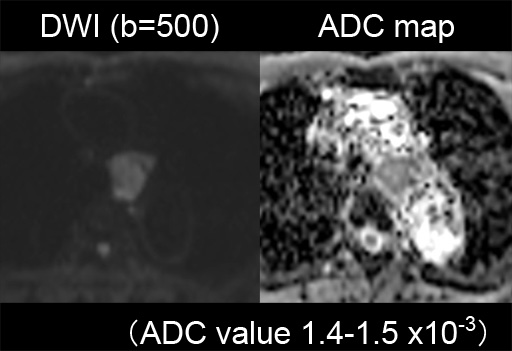

症例7 : 図12 DWI (b=500),ADC map